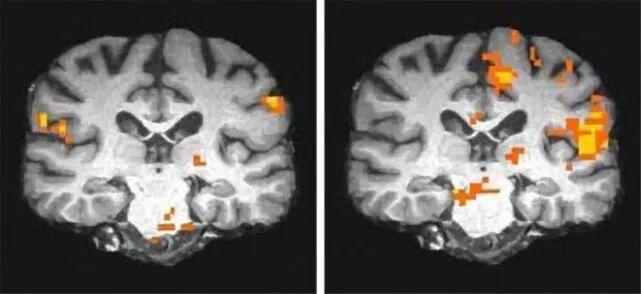

根据美国的一项调查,参加海湾战争的退伍军人患癌概率增加了4倍,染色体出现异常的情况更是增加了14倍(这些异常是引发癌症的关键,这意味着如果调查周期够长的话,患癌的概率会更高)。

不仅如此,使用了贫铀武器的士兵,其后代患有先天缺陷的概率也更高——是普通军人的2.2倍。

因为贫铀武器的使用,这些退役老兵在海湾战争遗留下的健康风险,被统称为“海湾战争综合症”,大约有25万士兵受到不同程度的影响。